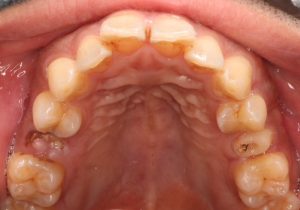

治療前

治療後